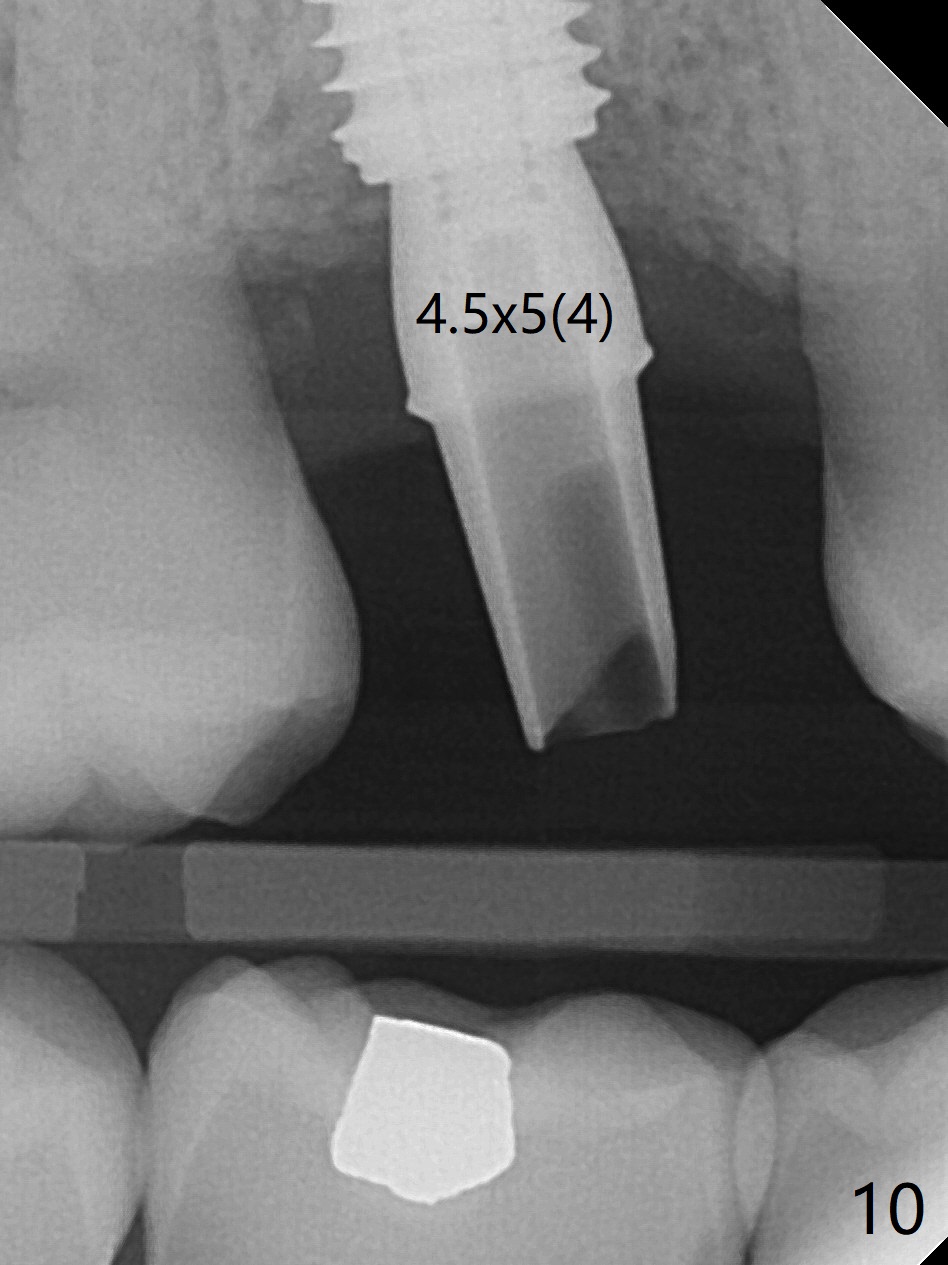

While the tooth #3 has a mesiodistal crack line, etiology may be due to chronic periodontitis with bruxism. After extraction, there is granulation tissue attached to the distobuccal (DB) root. The DB socket is larger than the mesiobuccal one (Fig.1). Osteotomy is initiated in the DB slope of the septum for 10 mm (Fig.2,3). Since there is ample apical bone, the depth of the osteotomy increases to 11.5 mm. When a 5x10 mm dummy implant is placed, primary stability is satisfactory (Fig.4 (yellow line: apical space)). The definitive implant remains the same dimension with deeper placement (Fig.5,6 (~ 20 Ncm)); with placement of a 6.5x4(3) mm abutment and Vanilla/Osteogen Graft (*), an immediate provisional is fabricated in place (without taking out for trimming) with sufficient clearance with the opposing dentition. It appears that the moderately long implant (10 mm) is able to achieve primary stability for immediate placement. When the provisional is removed 2 months postop, bone graft seems to be adhered to the socket (Fig.7). To improve local hygiene, the provisional does not return. The implant seems to have osteointegrated 3.5 months postop (Fig.8). The crown/abutment is loose approximately 1 year post cementation. Due to her daughter's contracting COVID 19, she postpones returning for approximately 1 year. The access hole is opened, crown/abutment (6.5x4(4) mm) removed, proximal contacts reduced, crown/abutment reseated without certainty. BW shows incomplete seating probably due to bony interference (Fig.9). A 5.5x4(4) mm can not be seated (bouncing, probably due to soft tissue interference). When a 4.5x5(4) mm abutment (UF) is seated, hand tightening is smooth, confirmed by BW (Fig.10). Two weeks later, the new crown is cemented intraorally. The crown/abutment is removed for cleaning. The abutment screw is torqued at 20 NCM.